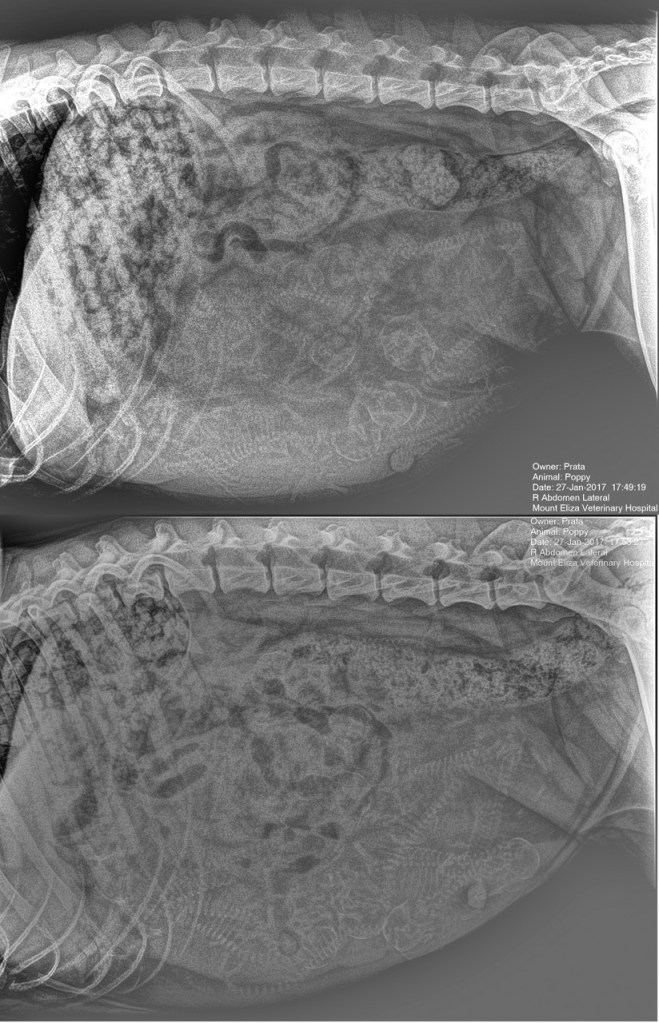

Poppy’s first pregnancy